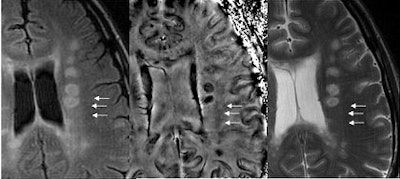

SWI's sensitivity to iron may open a new door into detecting lesions and the study of lesion specificity in MS.

| The far left and far right images are T2-weighted and both show numerous lesions. Some are seen on SWI and some are not in the SWI filtered phase images. However, some are seen better with SWI as dark regions (high iron content), and these may eventually be shown as markers for the specificity of the disease. Image courtesy of E. Mark Haacke, Ph.D., Wayne State University, Detroit. |